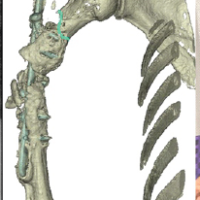

The previous hardware was removed after placing the patient in the supine position. A sterile dressing and below-knee posterior slab were applied with the ankle in neutral position (Figs. 6 and 7).